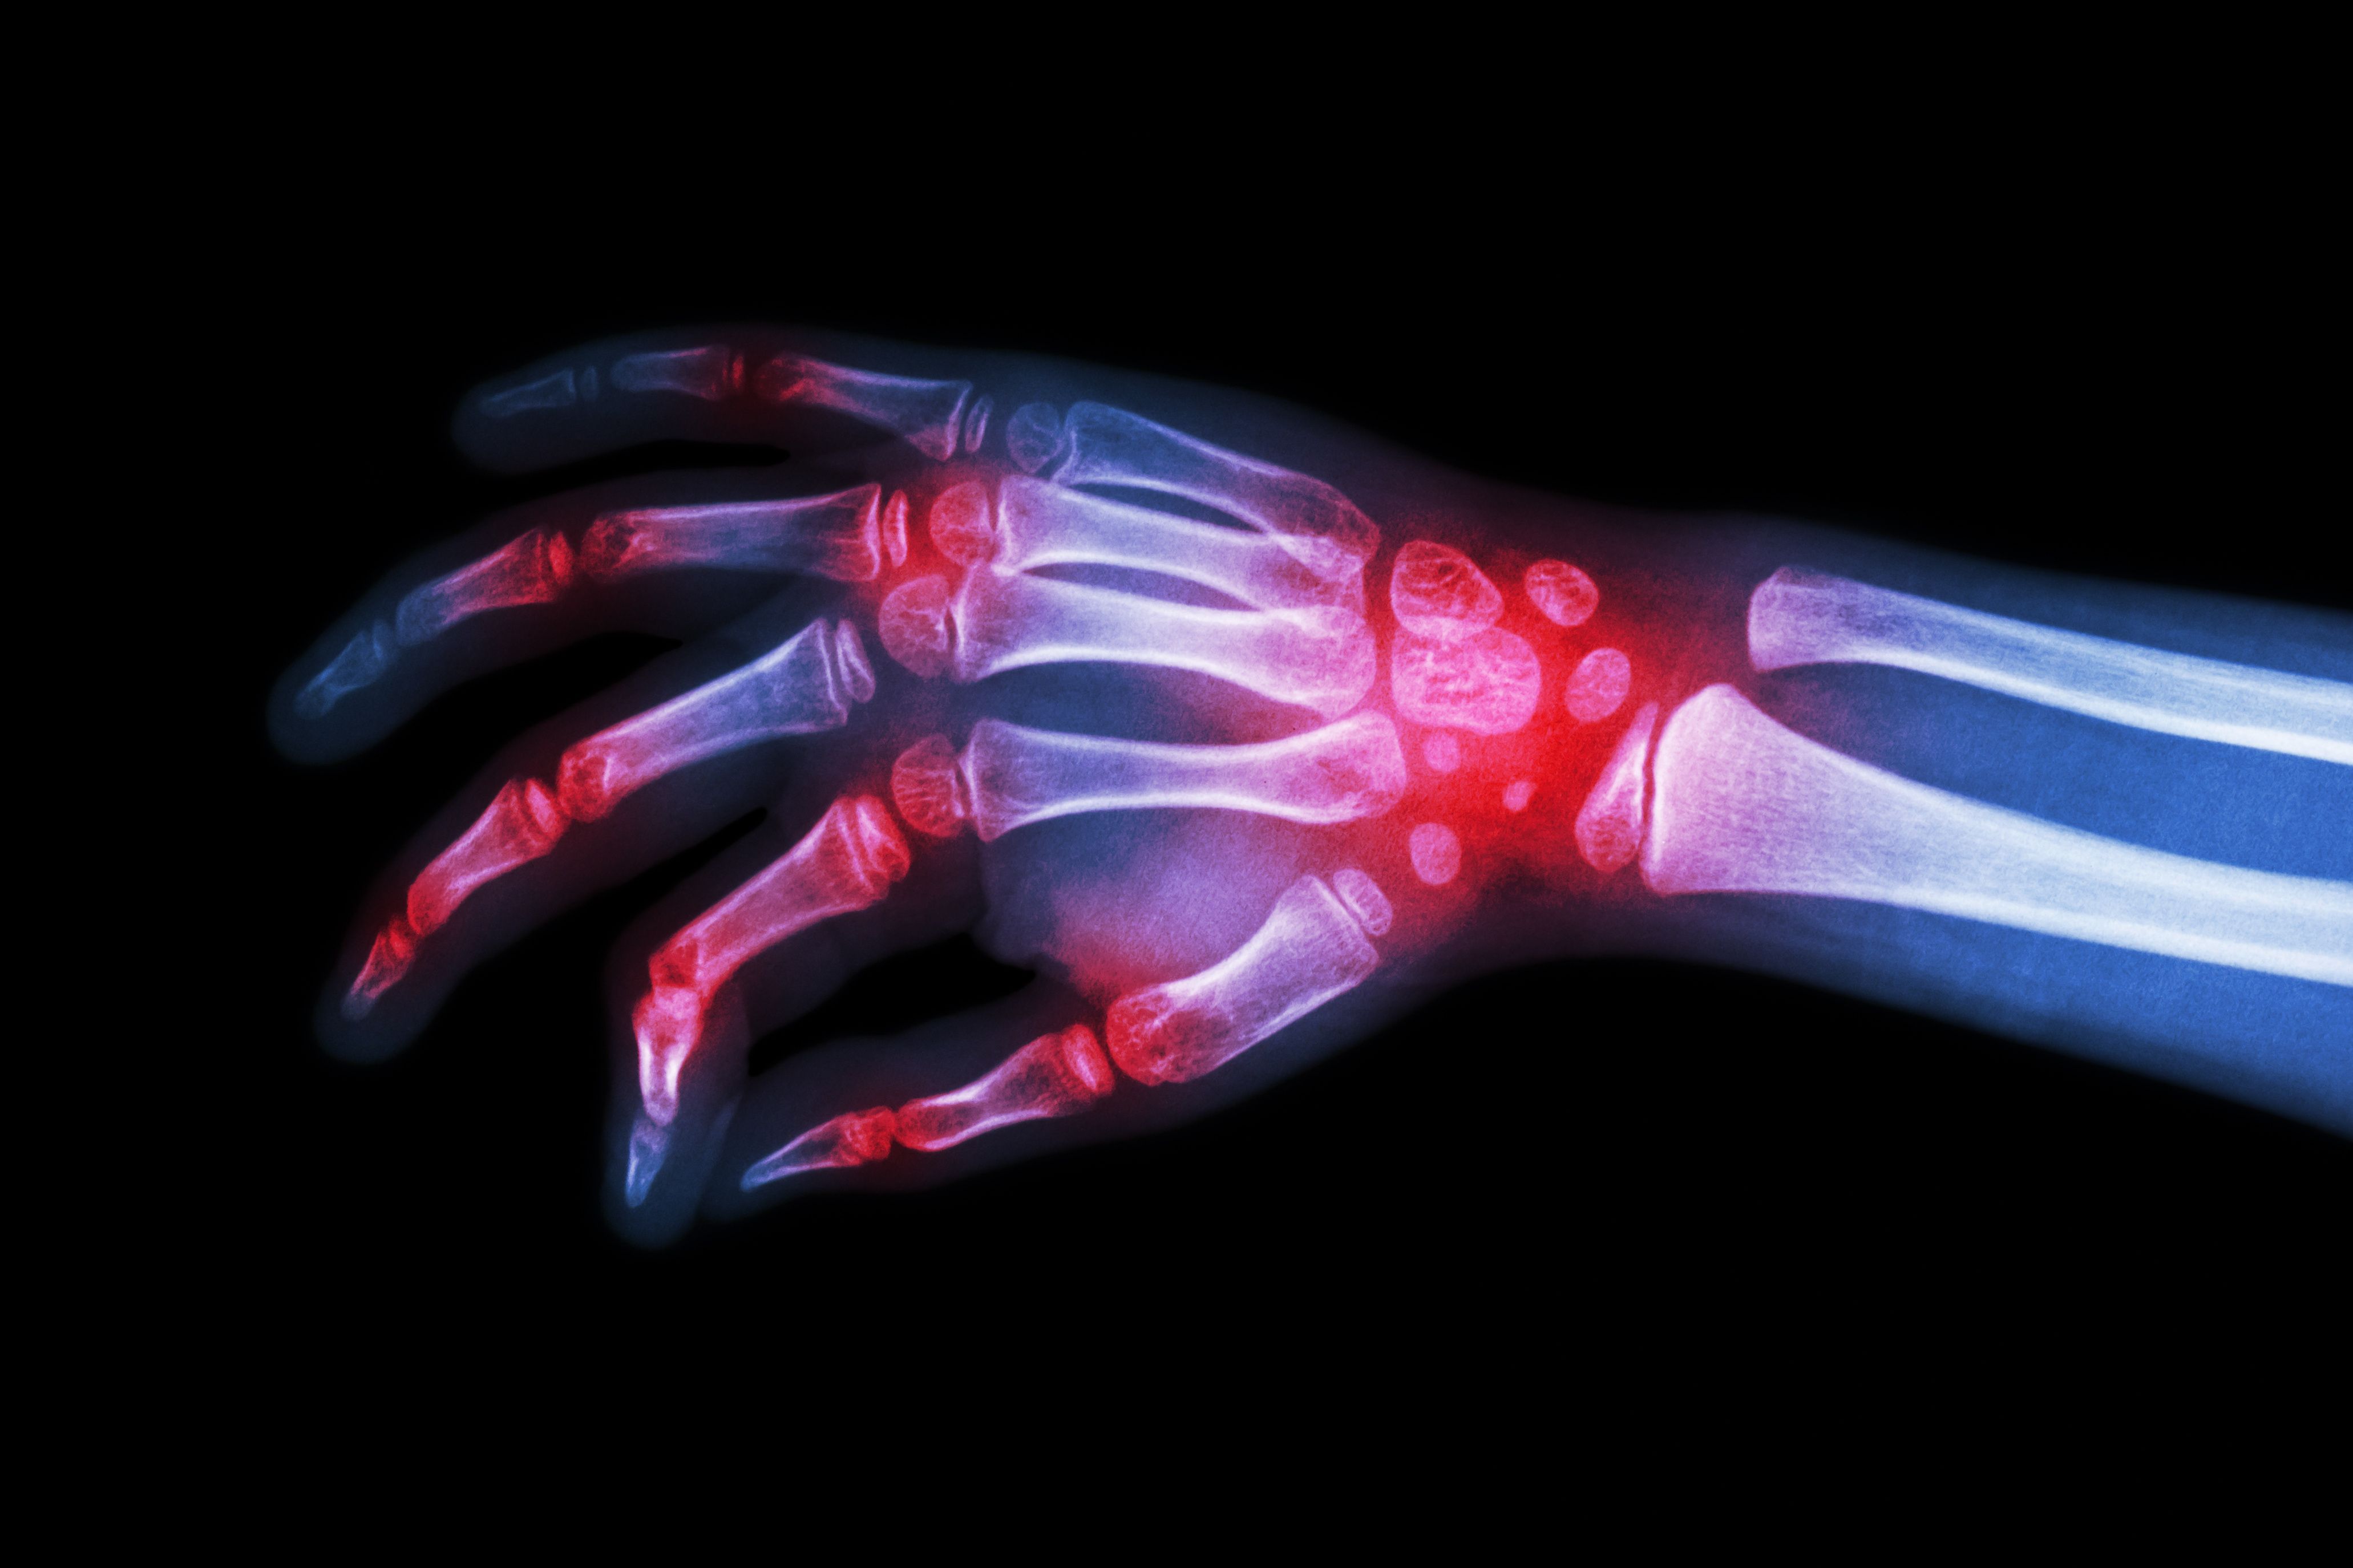

Rheumatoid Arthirtis X Ray | image credit: stockdevil - stock.adobe.com

In new findings presented at the American College of Rheumatology 2023 Convergence, successful results were identified in a new initiative for primary care physician (PCP) training in specialized care for rheumatoid arthritis (RA) patients in Native American communities that may deal with limited care in specialized fields.1